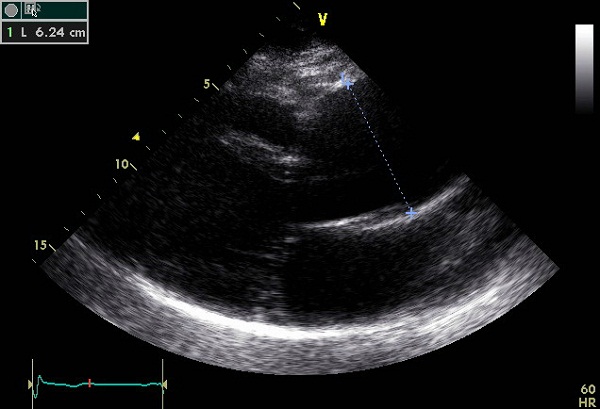

Aortic Regurgitation Smallest neck of the flow region – level of aortic valve Adjust color gain <3mm = Mild >6mm = Severe. 2 Regurgitant Volume 2 Methods of Calculating Continuity Method PISA Method Regurgitant Volume - CE This calculation is NOT accurate if ... Fetch Document